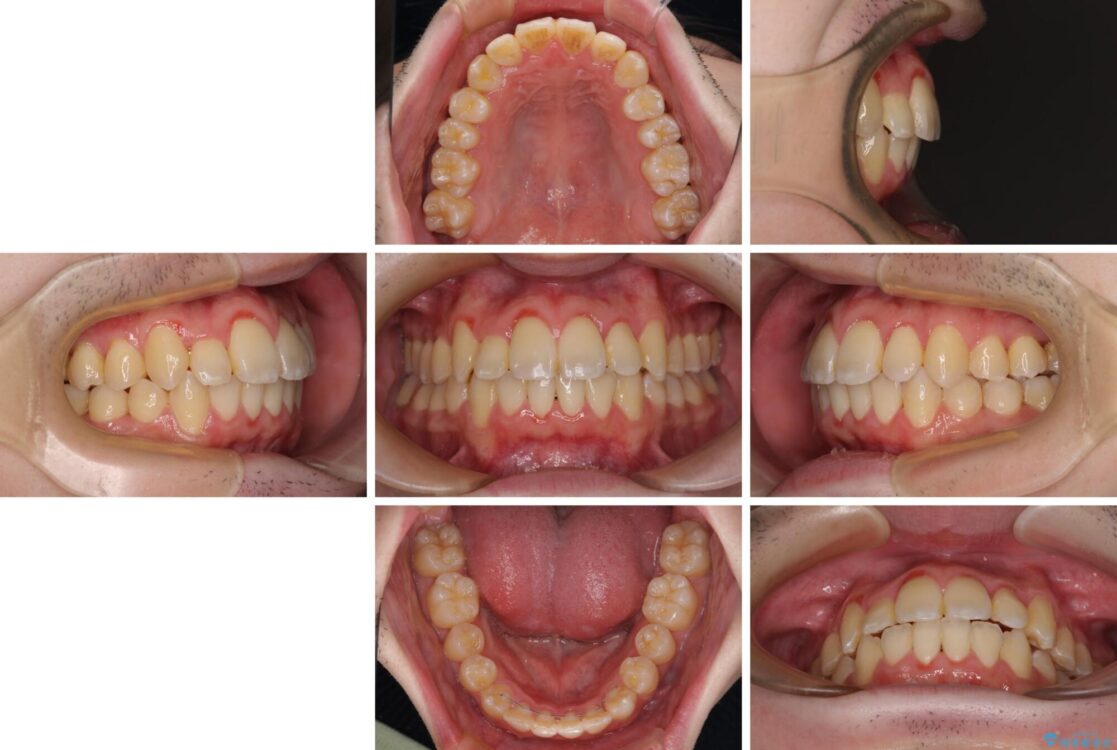

治療後

• 全顎的なクロスバイト 補助装置を用いてワイヤー矯正 治療後画像